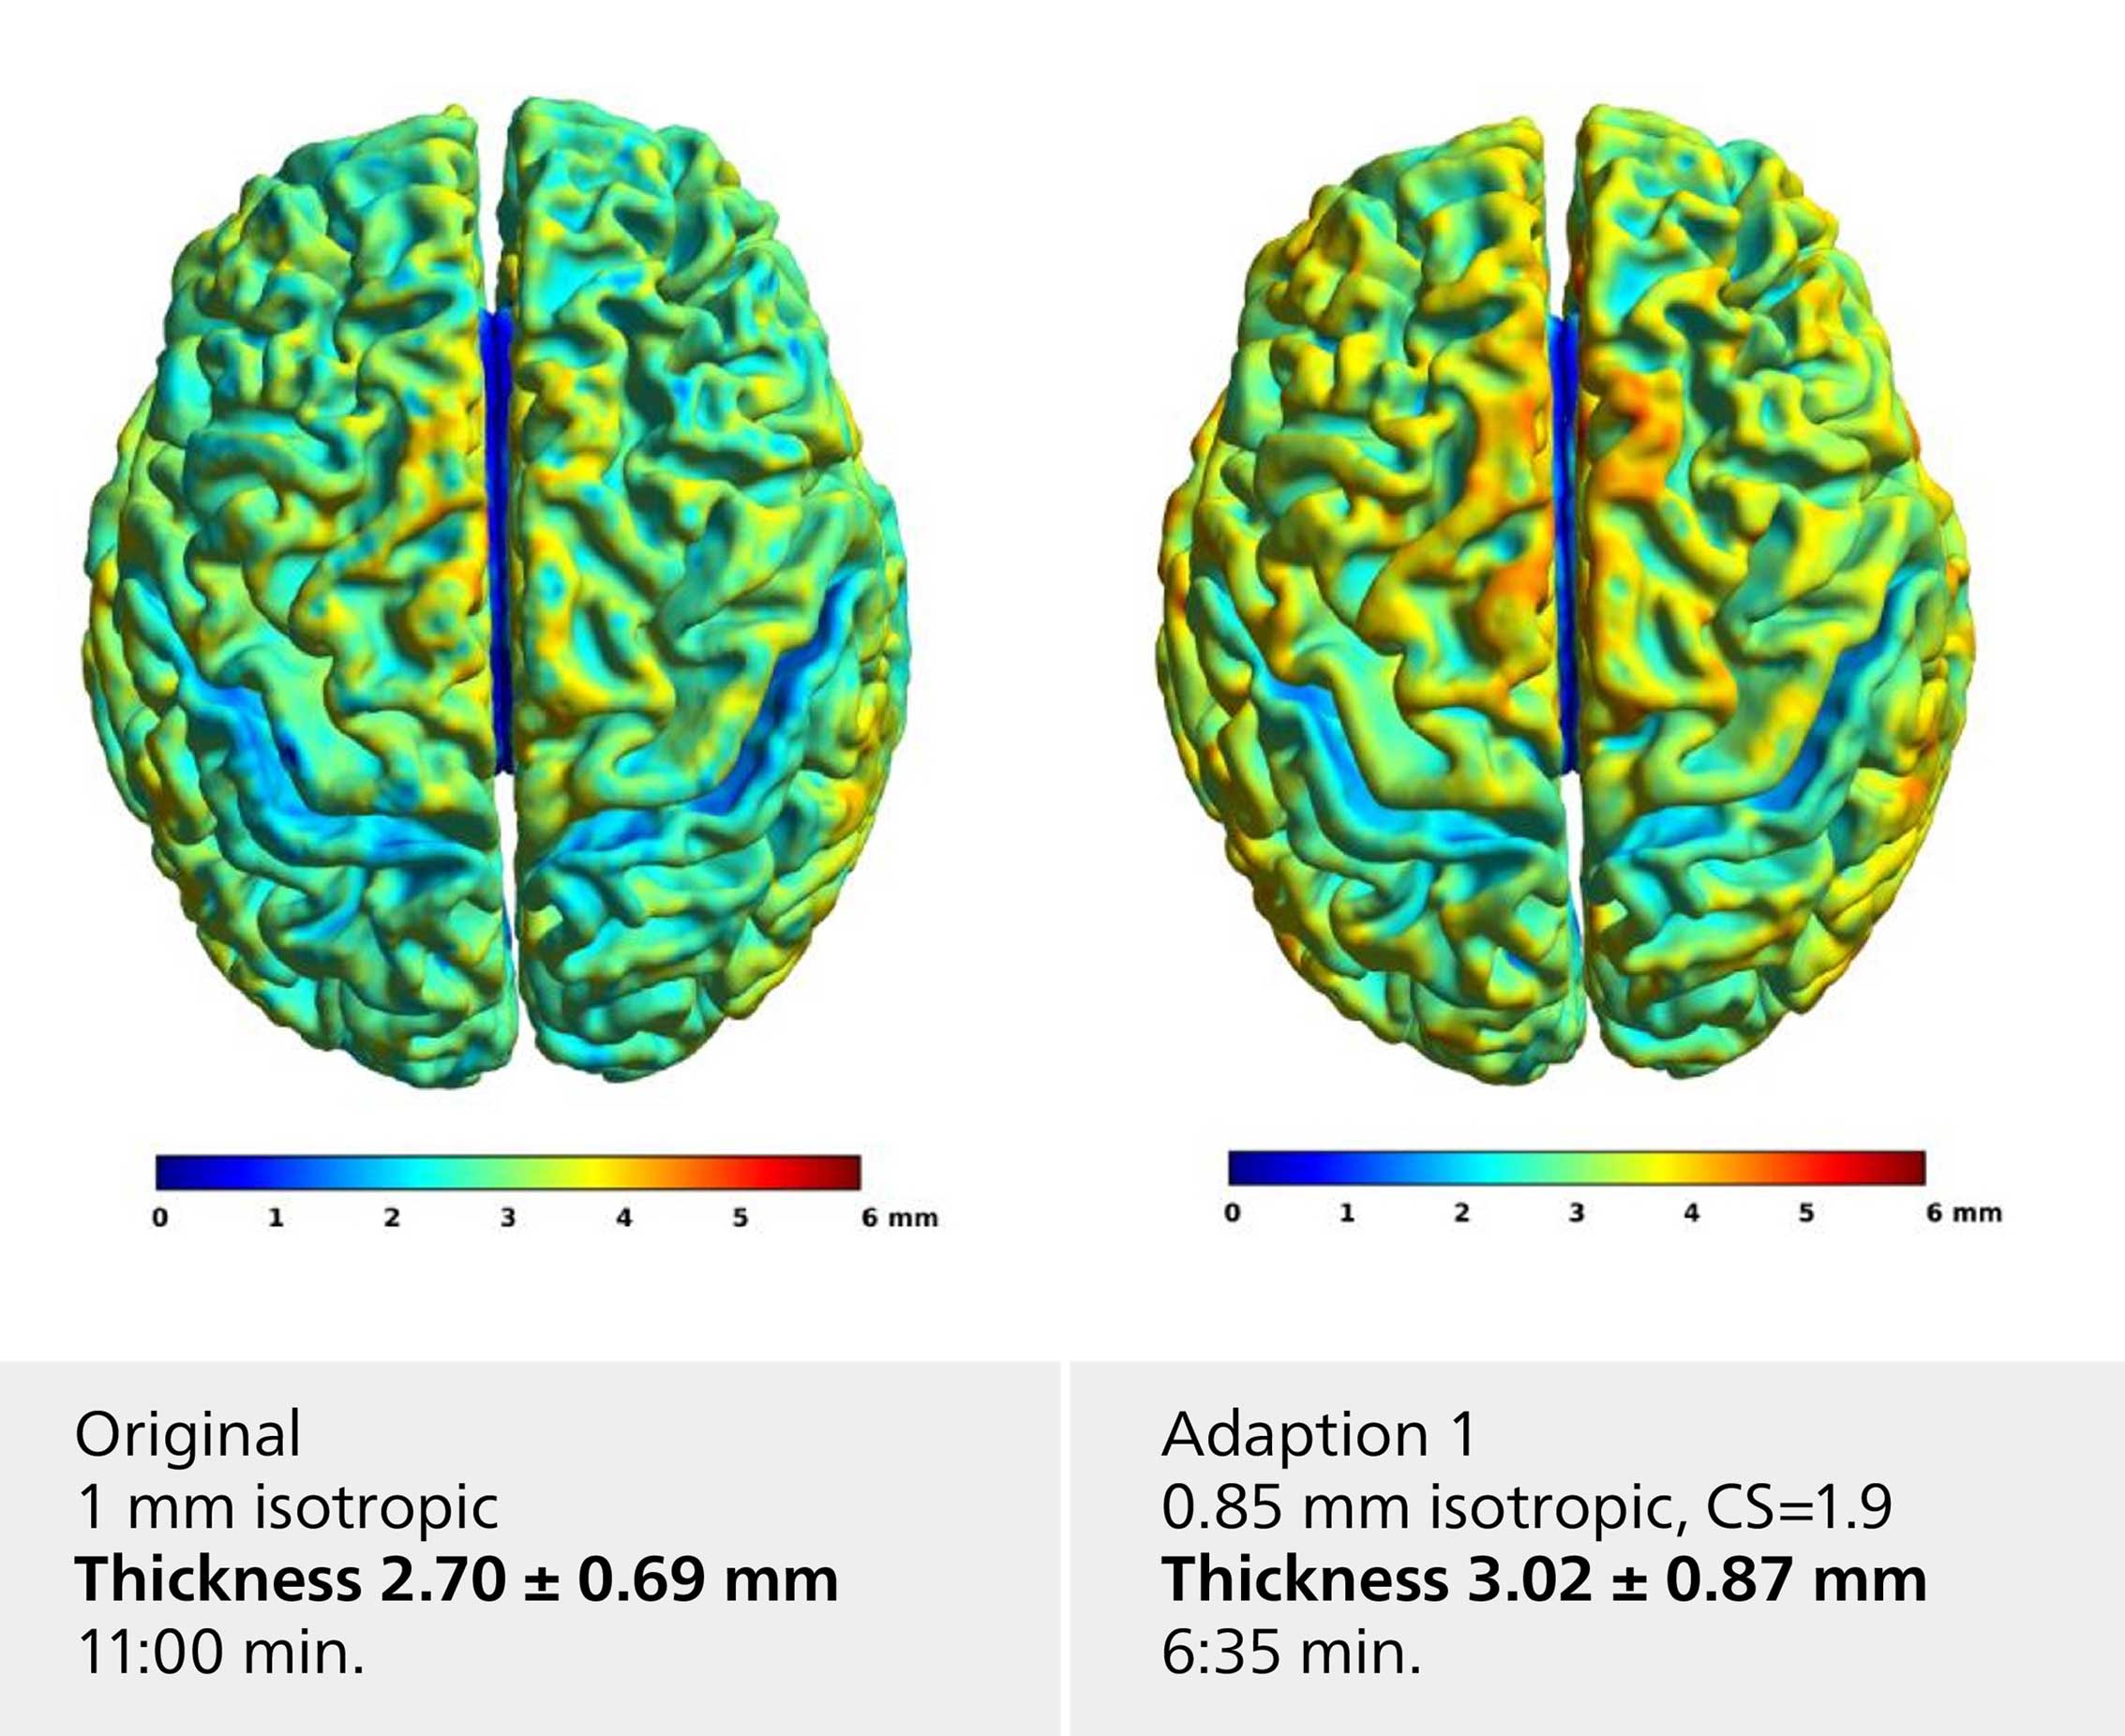

Voxel based morphometry

The neuroscience team compared their standard T1 brain morphometry sequence with alternate protocols facilitating Compressed SENSE. Selected examples shown here include adaption 1 with moderate CS=1.9, higher voxel resolution (0.85 mm), adaption 3 with CS=1.8 and 0.8 mm isotropic voxel size and the Philips protocol database default with CS=3.0 and 0.75 mm isotropic voxel size. All protocols resulted in comparable cortical thickness results with a slight decrease for higher CS-factors.

Voxel based morphometry

The neuroscience team compared their standard T1 brain morphometry sequence with alternate protocols facilitating Compressed SENSE. Selected examples shown here include adaption 1 with moderate CS=1.9, higher voxel resolution (0.85 mm), adaption 3 with CS=1.8 and 0.8 mm isotropic voxel size and the Philips protocol database default with CS=3.0 and 0.75 mm isotropic voxel size. All protocols resulted in comparable cortical thickness results with a slight decrease for higher CS-factors.